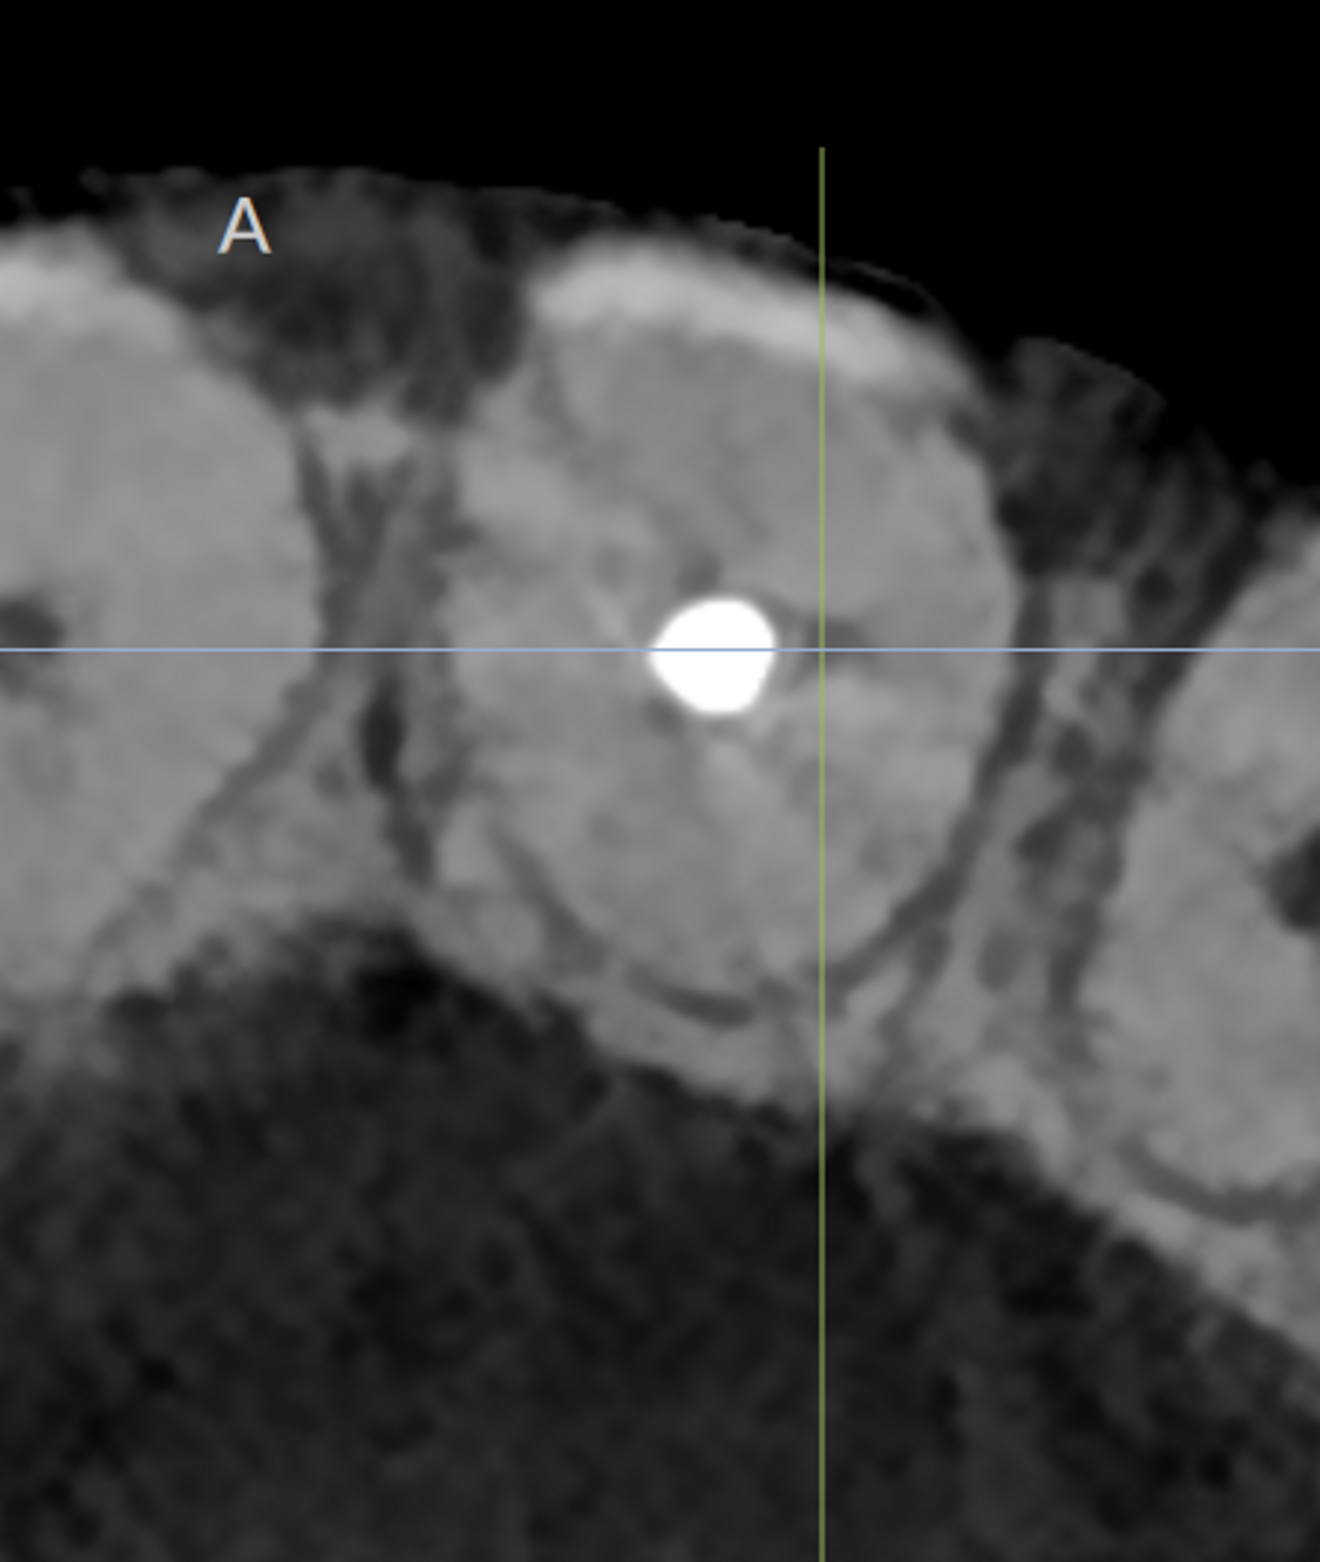

Starting with the diagnostic part, 3D imaging is an essential tool to complete the puzzle and find answers and to prepare a full treatment plan for a simple case as well as a complicated one. Artificial intelligence (AI) is a great addition regarding 3D imaging. For some time, I have been using the DTX Studio Clinic software, which has many AI features and enhanced image features that help me a great deal in my daily practice. When it is combined with the correct resolution and field of view for endodontics, it becomes a very powerful diagnostic tool. We recently upgraded our i-CAT unit to a DEXIS OP 3D unit, which has many advantages in the field of view and image quality, and it is just perfect when it is combined with the DTX software. Digital 3D imaging allows the discovery of unusual anatomy. In the case of a patient who presented complaining of pain and pressure on his tooth after undergoing root canal therapy some time before, careful reading of a CBCT scan of the area revealed a second canal in the central incisor and enabled us to locate the furcation (Figs. 1–3).

Figs. 1a & b: CBCT scan showing a second canal in the central incisor (E mode; field of view: 5 × 5 mm).

Fig. 2: Location of the furcation.